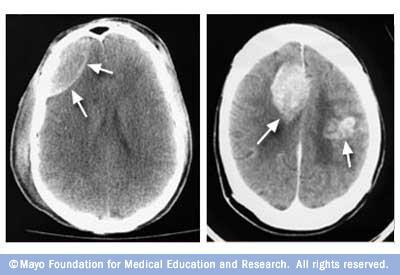

Many people with tattoos will eventually face the need of an mri scan for medical reasons. We explain the primary difference between the two diagnostic tools. Learn more about ct scans and how to be prepared. Ct scans of the brain can provide detailed information about brain tissue and brain structures. Do you know the difference between a pet scan and an mri?

Magnetic resonance imaging (mri) scans produce detailed images of the organs and tissues in the body. Vaccines & 3rd doses | testing | p. Mri scans may be able to detect physical and functional changes in the brain that could be markers for major depressi. Ct scans of the brain can provide detailed information about brain tissue and brain structures. Instead, it uses radio waves, a magnet. After much research, it is time to lay this question to rest. Read about the use of mri scan. Confidence, community, and joy sincerely media/unsplash many people will eventually fac. We explain the primary difference between the two diagnostic tools. Learn what that difference means. Mri scans may be carried out for a variety of reasons, and will be accordingly targeted at specific zones of the body. A pet/mri scan is an imaging test that combines pet and mri in one session. Scans of the brain and spinal cord, for instance, not only look for brain and spinal cord injuries but also for signs of.